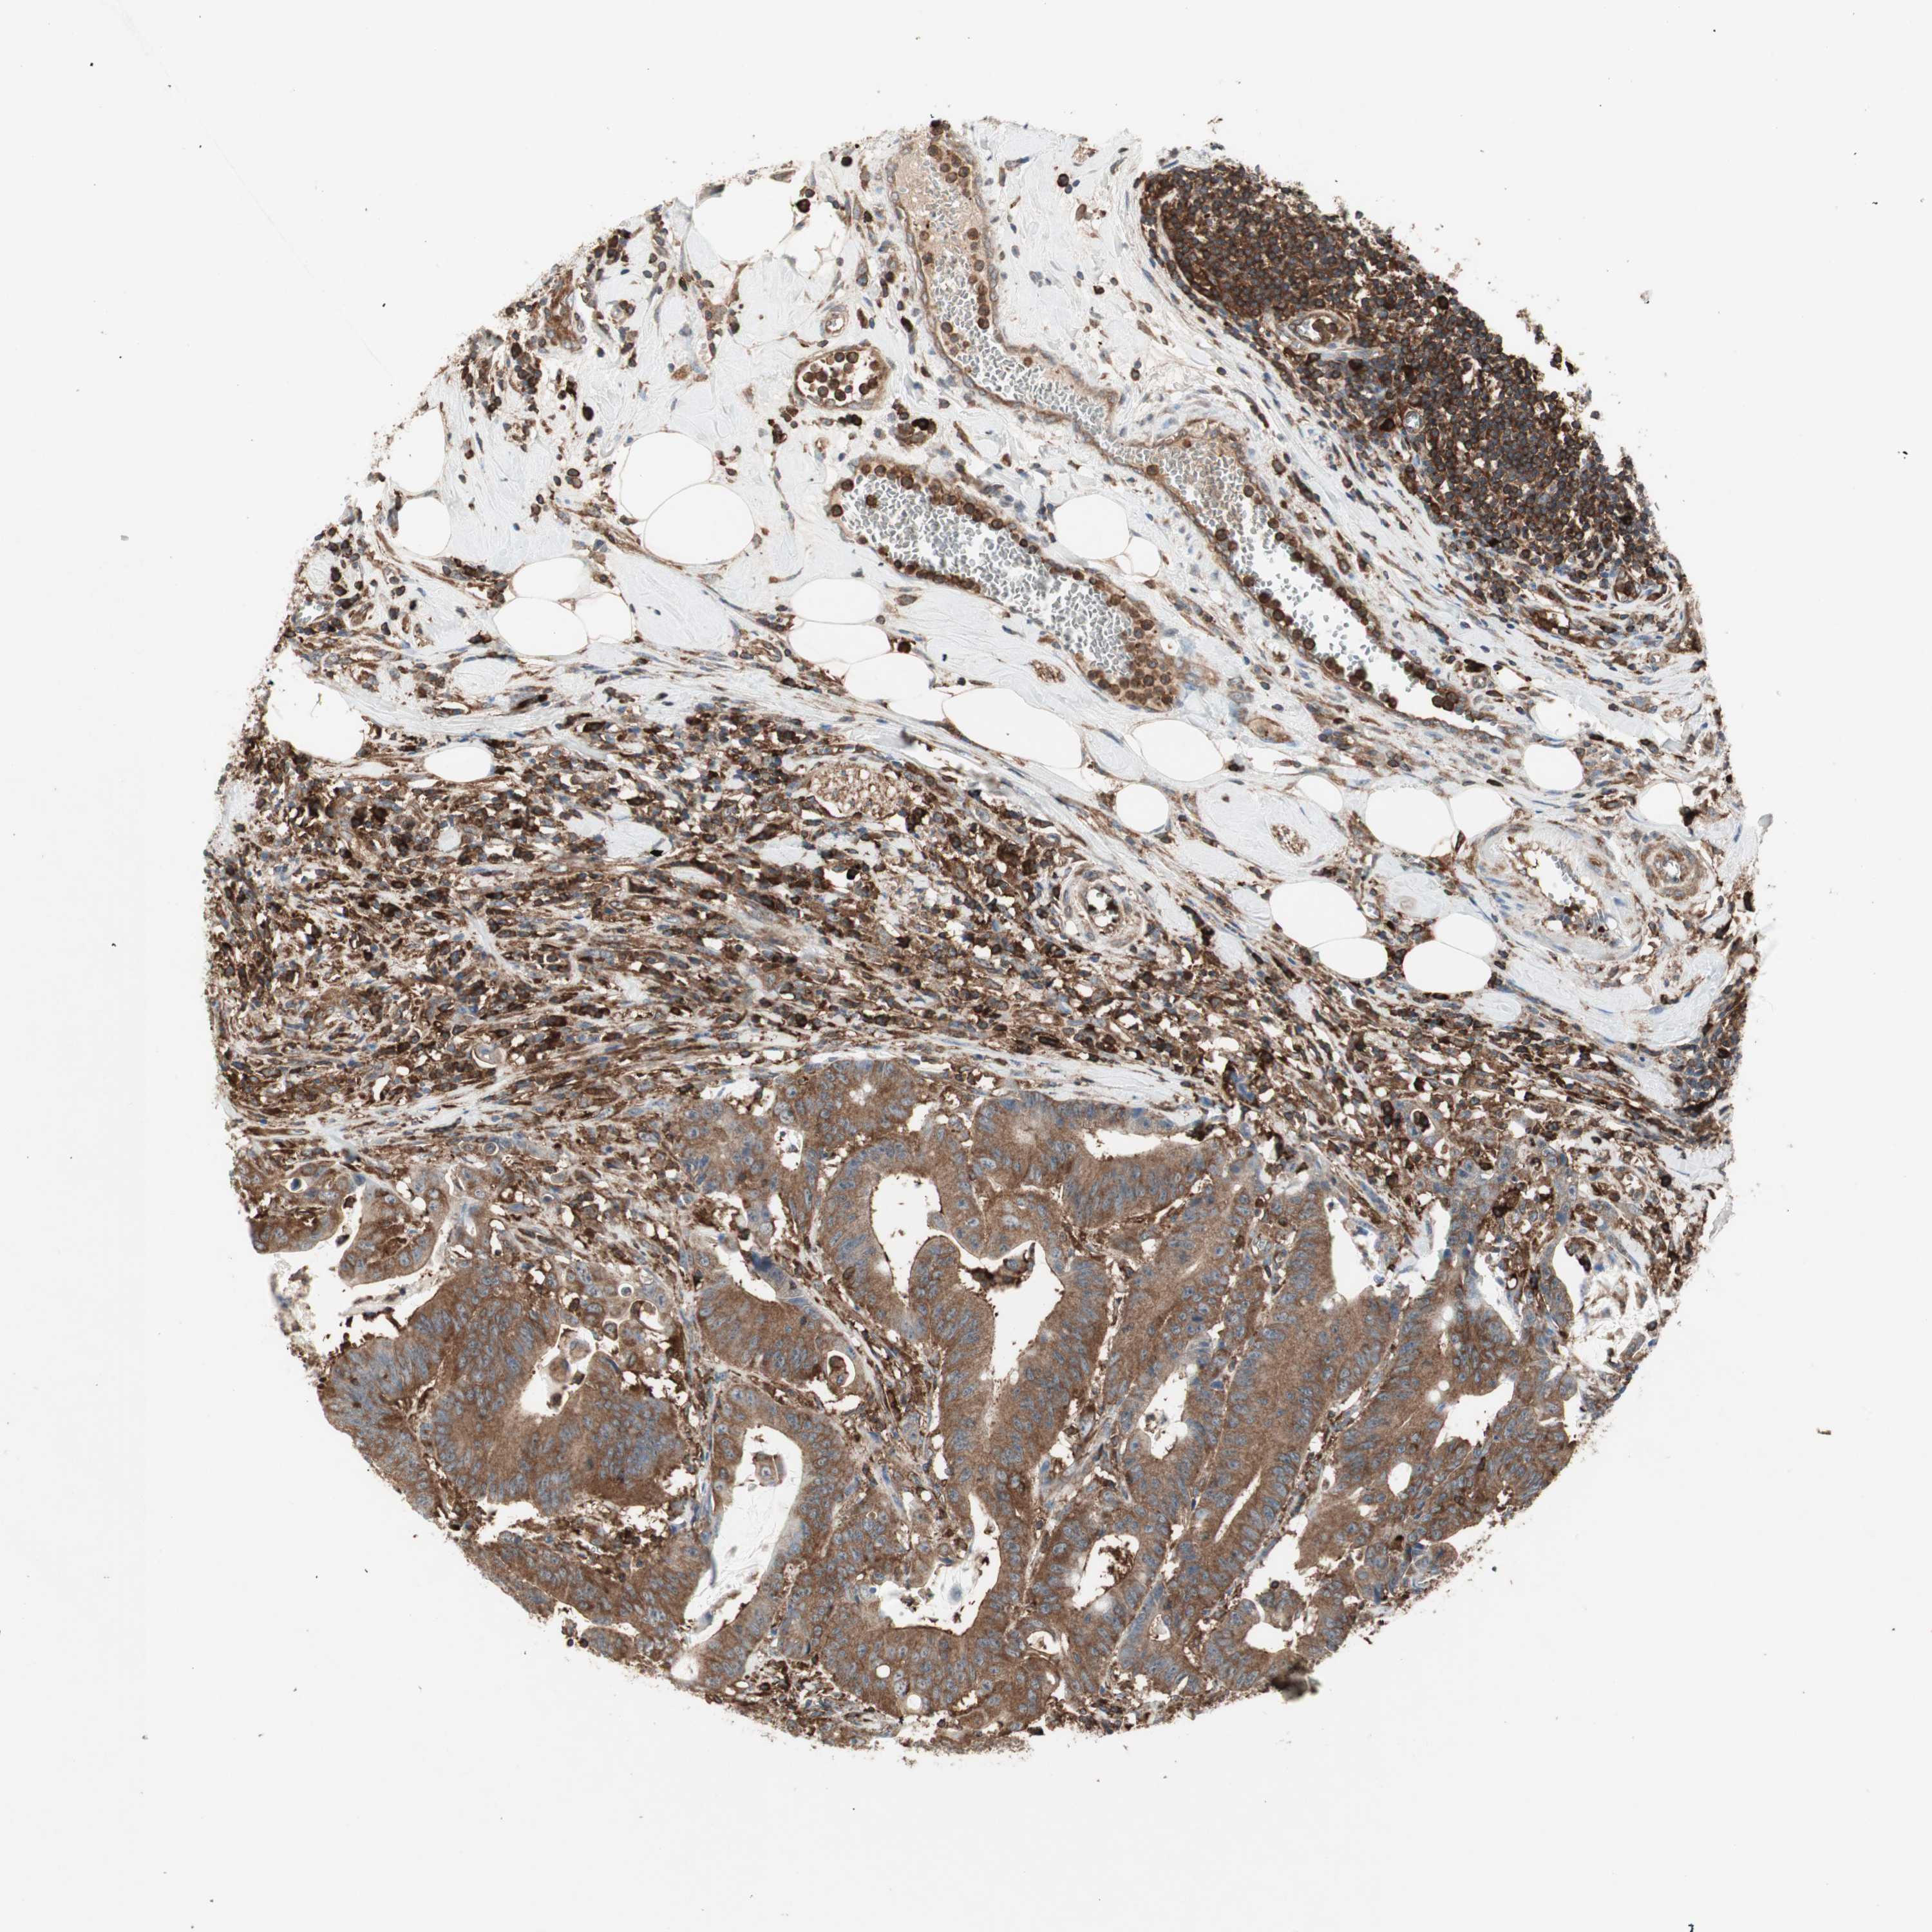

CANCER COLORECTAL CANCER Show tissue menu

Colorectal cancer

Human cancer

Colon adenocarcinoma